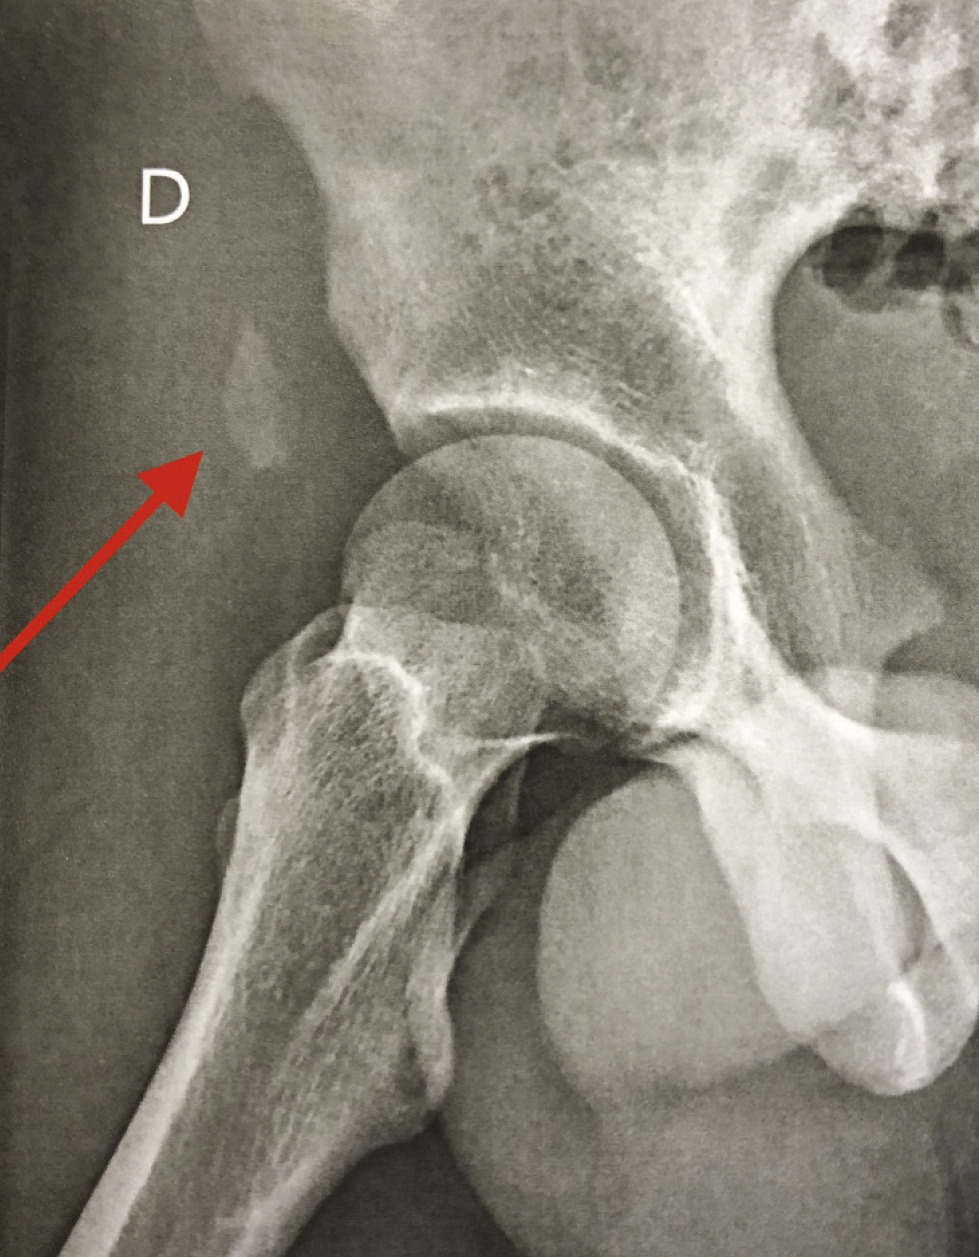

Ce jeune homme de 16 ans se présentait aux urgences pour une douleur brutale à la face antérieure

de cuisse droite apparue lors d’un mouvement de tir au football. La palpation notait une voussure proximale douloureuse. La radiographie montrait une avulsion osseuse proximale de l’épine iliaque

antéro-inférieure déplacée de 2,5 cm (figure). Ce déplacement justifiait la

réinsertion chirurgicale de cette avulsion osseuse du droit antérieur. Le patient avait totalement récupéré à 3 mois.